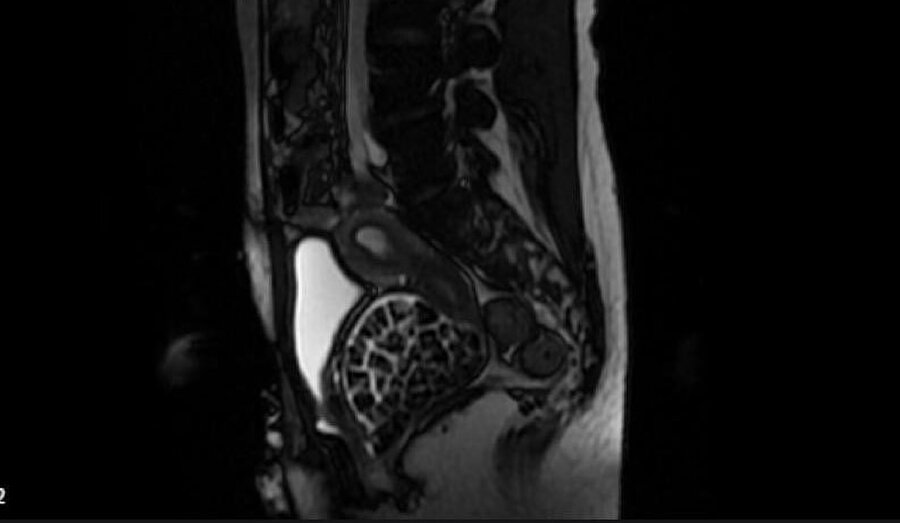

Hastasının durumuna yönelik konuşan Üroloji Uzmanı Doç. Dr. Erkan Erkan, "Hastamızın 2004 yılında doğduğunu ardından doğar doğmaz ekstrofi vezika dediğimiz 50 binde bir görülen bir anomaliden dolayı art arda ameliyatlar geçirdiğini öğrendik. 10 yaşında yine bir ameliyat geçirmişti, gerekli görüntüleme ve tetkiklerimizi yaptırdık. Normalde mesanesinin olması gereken yerin hemen arka kısmında taşlarla dolu bir kese olduğunu gördük, bunun üzerine ek görüntülemeler; MR çektirdik. Hastamız çelişkili açıklamalar almıştı, kendi radyolojik kliniğimiz ve edindiğimiz konsültasyonlarda taşların mesanede değil vajinal boşlukta oluştuğunu düşündük, bir planlama yaptık. Kadın doğum hocamızın da çabasıyla taşları tamamen temizledik ardından ileride normal bir hayat sürmesi bakımından oraya plastik cerrahi yaptık. 287 adet taş çıkardık, pratikte gerçekten görünce çok şaşırdık çünkü bu aynı zamanda literatürde çok nadir görülen bir olay. Biz ameliyata hazırlanırken de teorik olarak biraz araştırdık. Literatürde gördüğümüz kadarıyla buna benzer bu tanıma uyan bir vaka vardı. Literatürde sanırım yayınlanmış 2’nci vaka olacak. Farkındalık çok önemli, bilinçli bir hastamız vardı. Doğumsal anomaliyle doğan çocuklarımızda ileride bunlara bağlı bazı sıkıntılar çıkabileceğinin öngörülmesi lazım. İlgili tedavilerini alsalar bile düzenli takiplere gelmeleri gerekiyor. İleride eğer dikkat etmezse ki zannetmiyorum, tekrarlayabilir. Bu rahatsızlık ekstrofi vezikal epispadias durumu çok nadir bir durum" dedi.

Karnı adeta taşlarla doluydu

Genç kızın uzun süredir devam eden karın ağrısı olduğunu söyleyerek sözlerine başlayan Jinekolojik Onkoloji Uzmanı Op. Dr. Emin Erhan Dönmez, "Mesane taşları olduğu düşünülerek daha büyük bir hastaneye refere edilmiş. Aramızda mini bir konsey yaparak muayene ettik. Vajen bir hazne görevi görerek orada durağan bir idrar, uzun süre beklediği için idrar içindeki minerallerde çökerek taşlar oluşmuş. Mesanedeki idrarın vajene akmış olabileceği ve vajende göllenen idrar nedeniyle taşların burada oluşacağını düşündük, ameliyatımızı planladık. Ameliyata tanı amaçlı girmiştik, sistoskopi (Mesane gibi idrar yollarını kapsayan kısımlardaki rahatsızlıkların teşhis ve tedavisinde kullanılan endoskopik bir yöntem) dediğimiz ameliyatı Erkan Hocam ile birlikte gerçekleştirdik. Önce mesaneyi bir görüntüledik, mesane tabanına yaklaşık 2-3 cm’lik bir alandan vajene fistülize olduğunu gördük. Mesaneden vajene geçtiğimiz esnada tüm vajenin taşlarla dolu olduğunu gördük. Tanı amacıyla girdiğimiz ameliyatta her şey de olağan gittiği için tedaviye geçtik. Taşların çıkabileceği kadar bir genişlik sağladık. Daha sonra yaklaşık en büyüğü 2,5 cm boyutlarında olan, irili ufaklı 287 tane taşı ameliyat esnasında çıkarmış olduk. Taşların tekrarlamaması için idrarın göllenmemesi, en azından dışarıya rahatça boşalabilmesi için vajinal rekonstrüksiyonu sağladık. Ameliyatta da herhangi bir problem yaşamadık. Literatürü Erkan Hocam ile birlikte değerlendirmiştik. Primer olarak vajende birikmiş olan bu kadar çok sayıda taşla ilgili bir makale görmedik, rastlamadık" dedi.